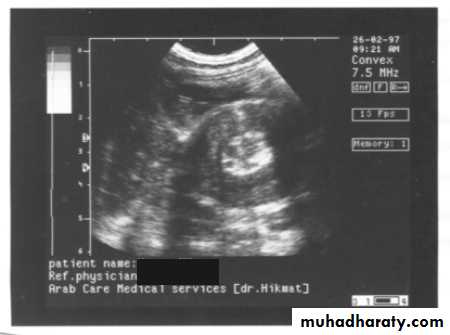

2. US